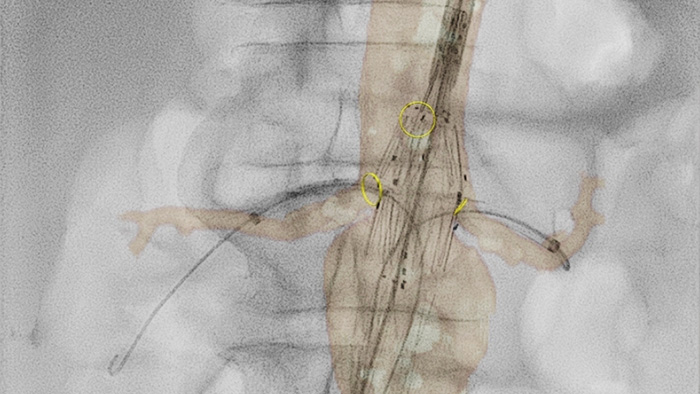

VesselNavigator provides an intuitive and continuous 3D roadmap based on existing CTA and MRA datasets to guide you through vasculature during aortic procedures. One study1 showed an average of 170 ml contrast reduction during endovascular repair of complex aortic aneurysms with the use of VesselNavigator CTA image fusion guidance.2 Another study showed a reduction in average procedure time from 6.3 to 5.2 (1.1) hours during FEVAR/BEVAR with VesselNavigator CTA image fusion guidance.3